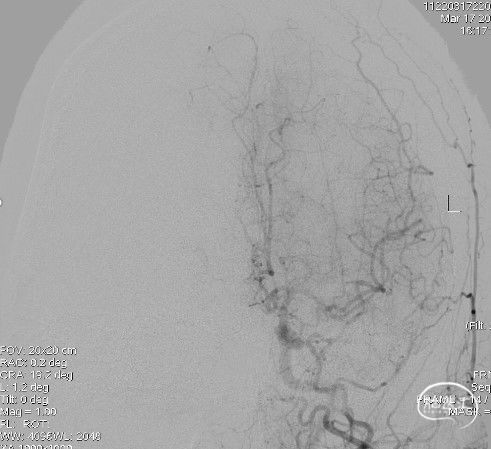

左颈内动脉:大脑前动脉通过前交通动脉向右侧代偿供血,左侧大脑中动脉分叉部分支闭塞。

左侧颈总动脉正位: